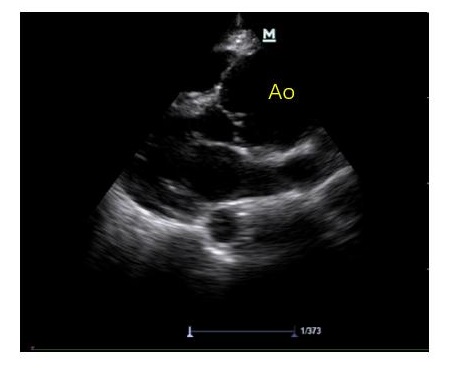

不论是在VV-ECMO或VA-ECMO运行过程中,利用床旁超声对心脏功能评估及每日监测非常重要。

① 扫查切面:根据患者实际情况选择需要的切面,并需将多切面结合补充,综合评估。可根据需要选择经食道超声心动图检查。

② VV-ECMO 床旁超声通过LVOT VTI和LVOT直径可快速测算出心排血量,从而制定匹配的ECMO流量;并结合血管超声和肺部超声共同对患者有效血容量进行调整,保证氧供;联合机械通气者监测右心舒张末内径,右心收缩功能、三尖瓣反流等肺动脉高压的超声证据,及时发现继发性肺动脉高压。VV-ECMO运行过程中,心脏超声探查发现合并心功能减退时,可更换至VA/VAV支持模式。

③ VA-ECMO 对患者心脏收缩、舒张功能进行评估和监测是确定理想ECMO流量和支持力度的前提。根据患者心脏功能来协助容量管理和流量调节贯穿于整个治疗过程中。

A、左心:观察左心室壁运动情况,测量左心室收缩和舒张功能,评估二尖瓣及主动脉瓣瓣膜功能。对心功能连续、及时评估可协助制定流量支持力度和决定撤机时机。通过连续性监测左室舒张末内径变化、主动脉瓣开合情况,评估左心室后负荷,制定左室减压时机与策略(图 20)。当患者出现心腔内血流显影时,形成血栓风险增加,对心腔进行密切监测,调整抗凝治疗策略,预防心室内血栓形成。

B、右心:右室大小、右心与左心比例可用于评估容量状态和右心后负荷即肺动脉压力情况,还可通过测量三尖瓣环收缩期运动幅度(TAPSE)半定量评估右心收缩功能,面积法计算右心射血分数、三尖瓣环组织多普勒测量其运动速度均可对右心收缩功能进行评估。